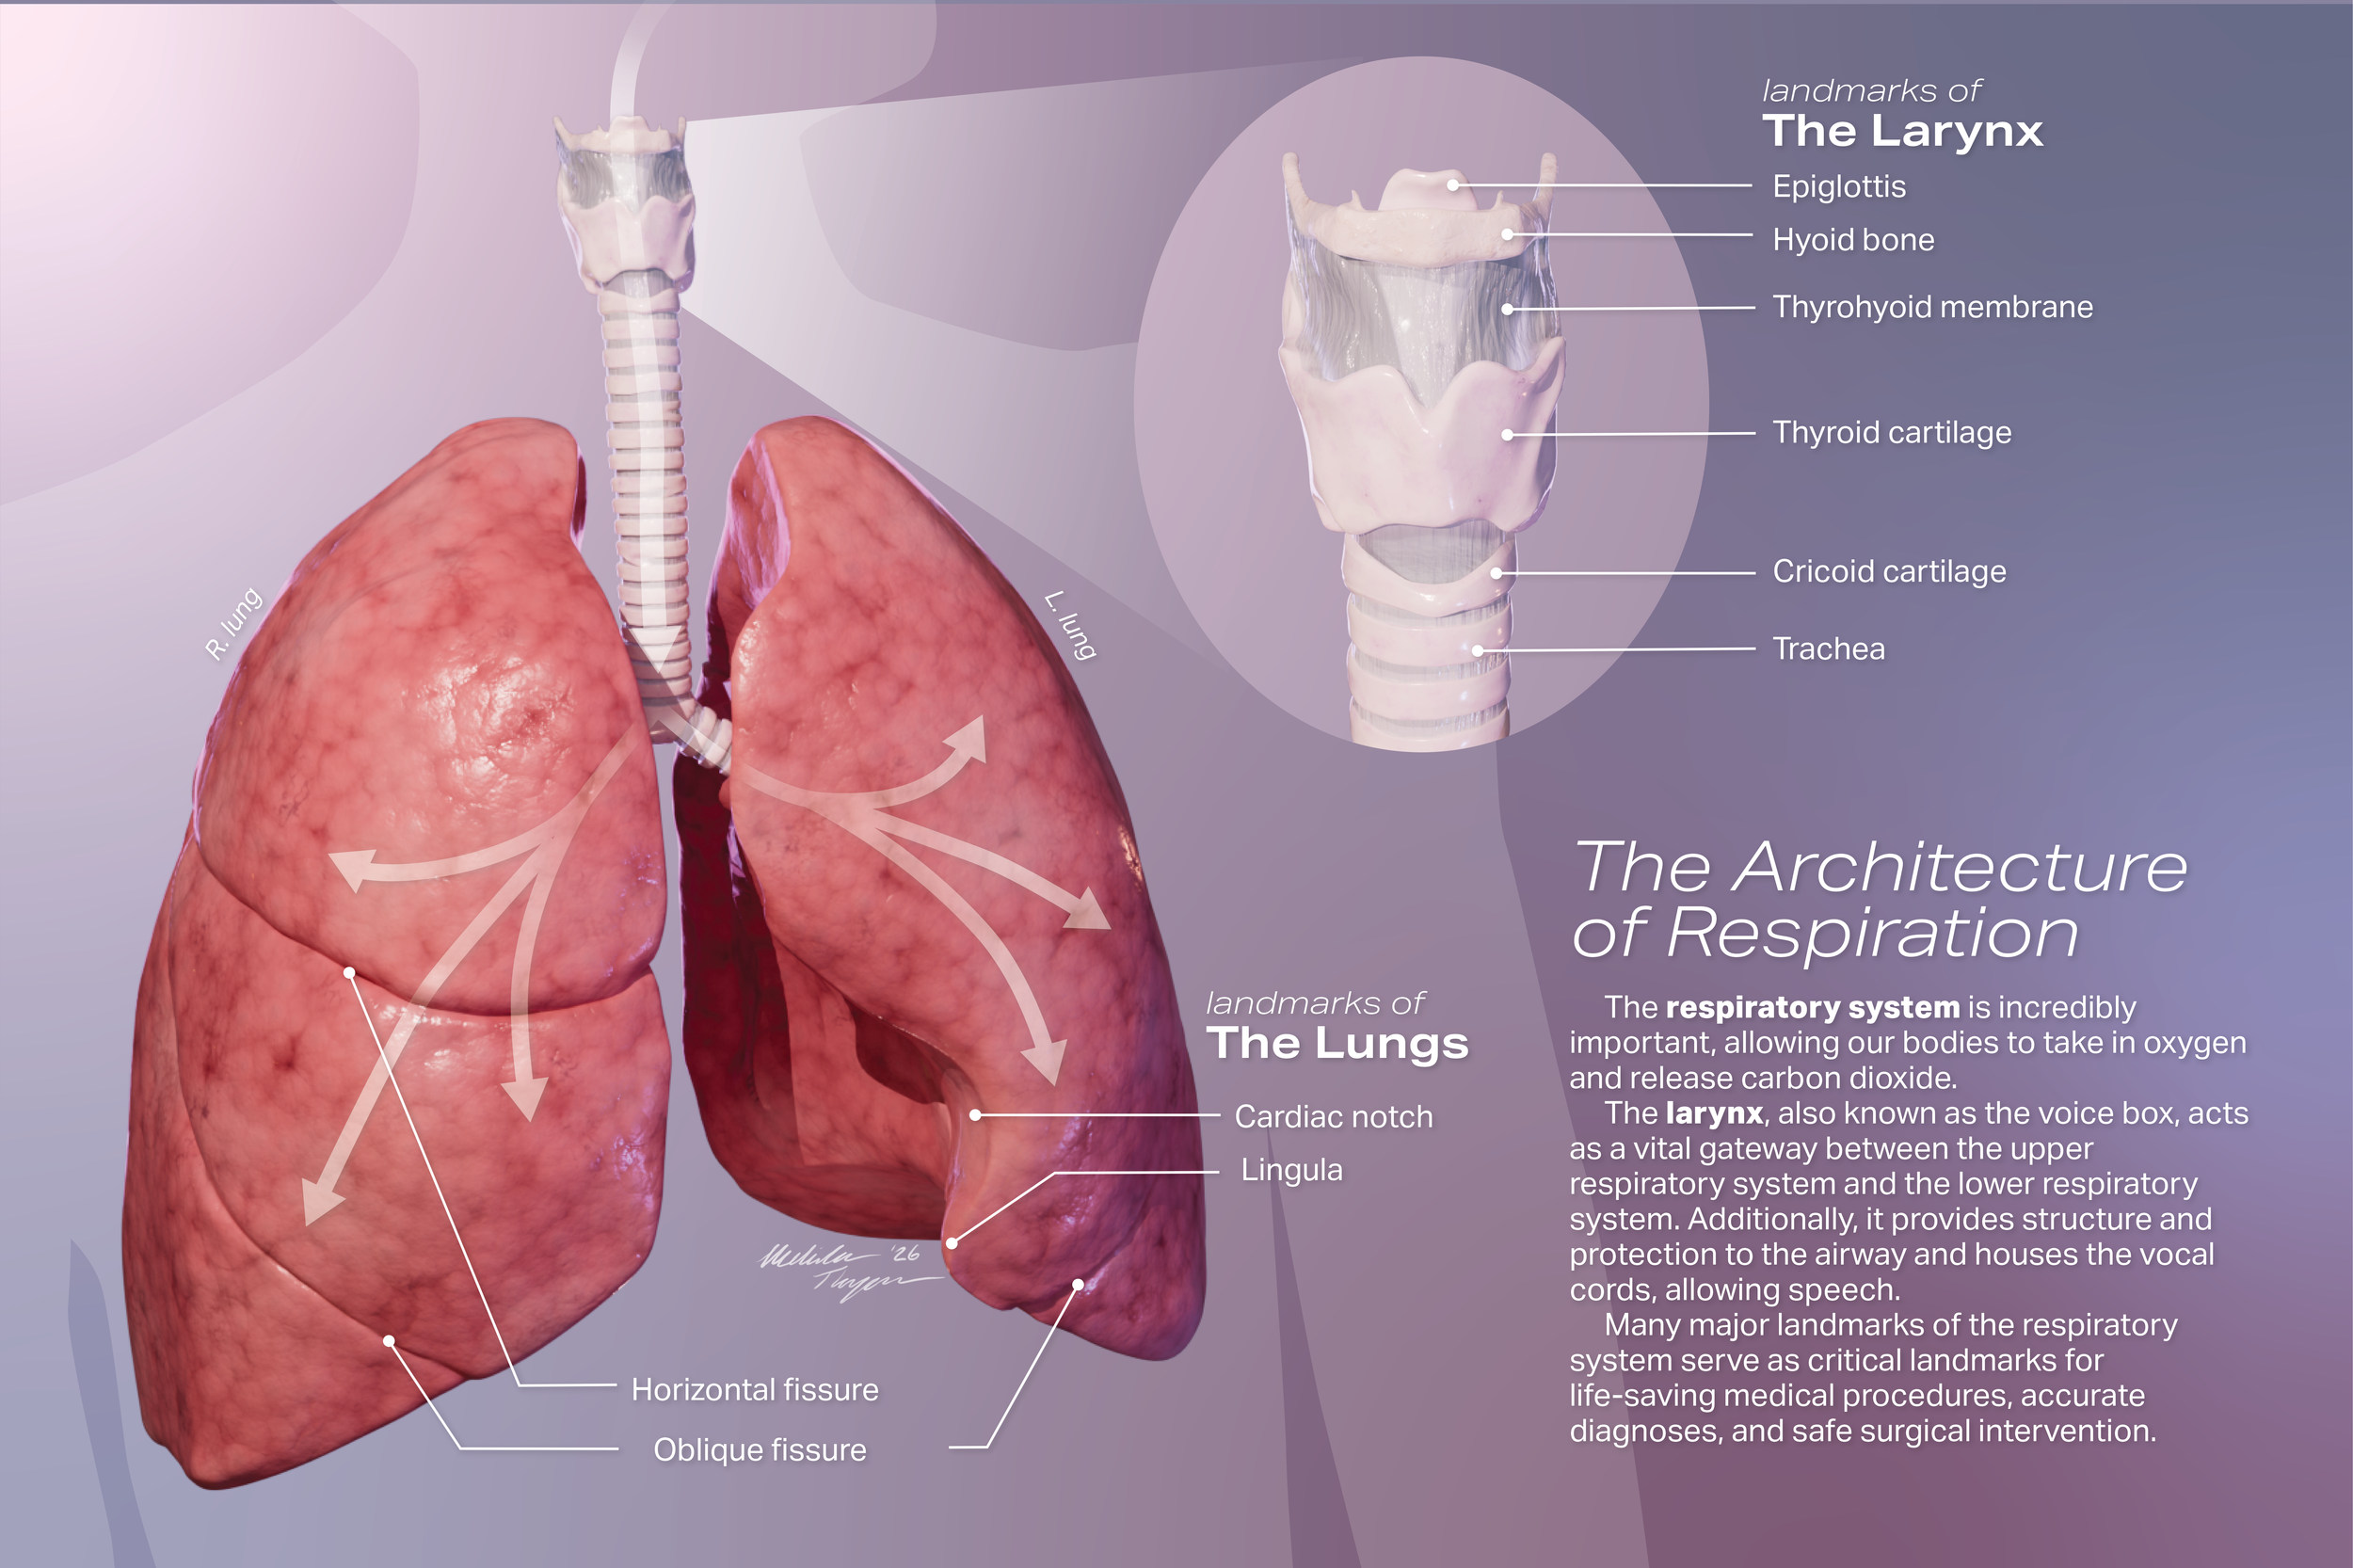

Educational Poster: The Architecture of Respiration